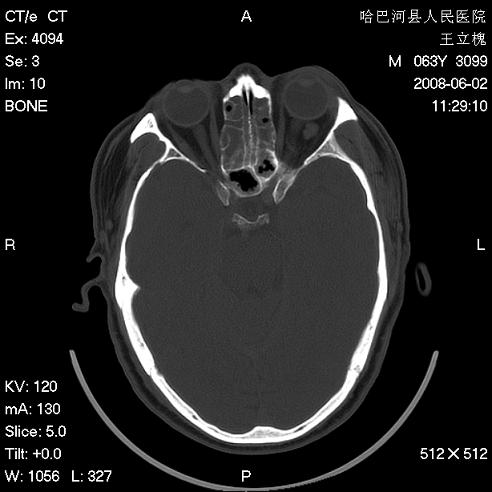

标题: CT13803:反复性鼻塞、流涕一年余 [打印本页]

标题: CT13803:反复性鼻塞、流涕一年余

全组副鼻窦炎 肌锥内高密度灶。建议进一步检察检查

1、全组副鼻窦炎。

2、左眼眶肌锥内病变,小血管瘤?建议增强。

1)全副鼻窦炎(左侧上颌窦黏膜下囊肿或息肉)。2)左眼眶肌锥内不规则小结节状软组织密度影;考虑为小血管瘤可能。建议行ct增强扫描检查。

全组副鼻窦炎,左侧肌锥内不规则形软组织肿块影,与眼外肌密度相当,左侧视神经受压,肿块与视神经及眼外肌分界清晰,眼外肌无增粗,眶壁无破坏,球后脂肪间隙不模糊,考虑良性改变,小血管瘤或神经源性肿瘤可能,建议增强扫描。

谢谢,增强扫描做了,眶内病灶与海绵窦同步明显强化,血管瘤